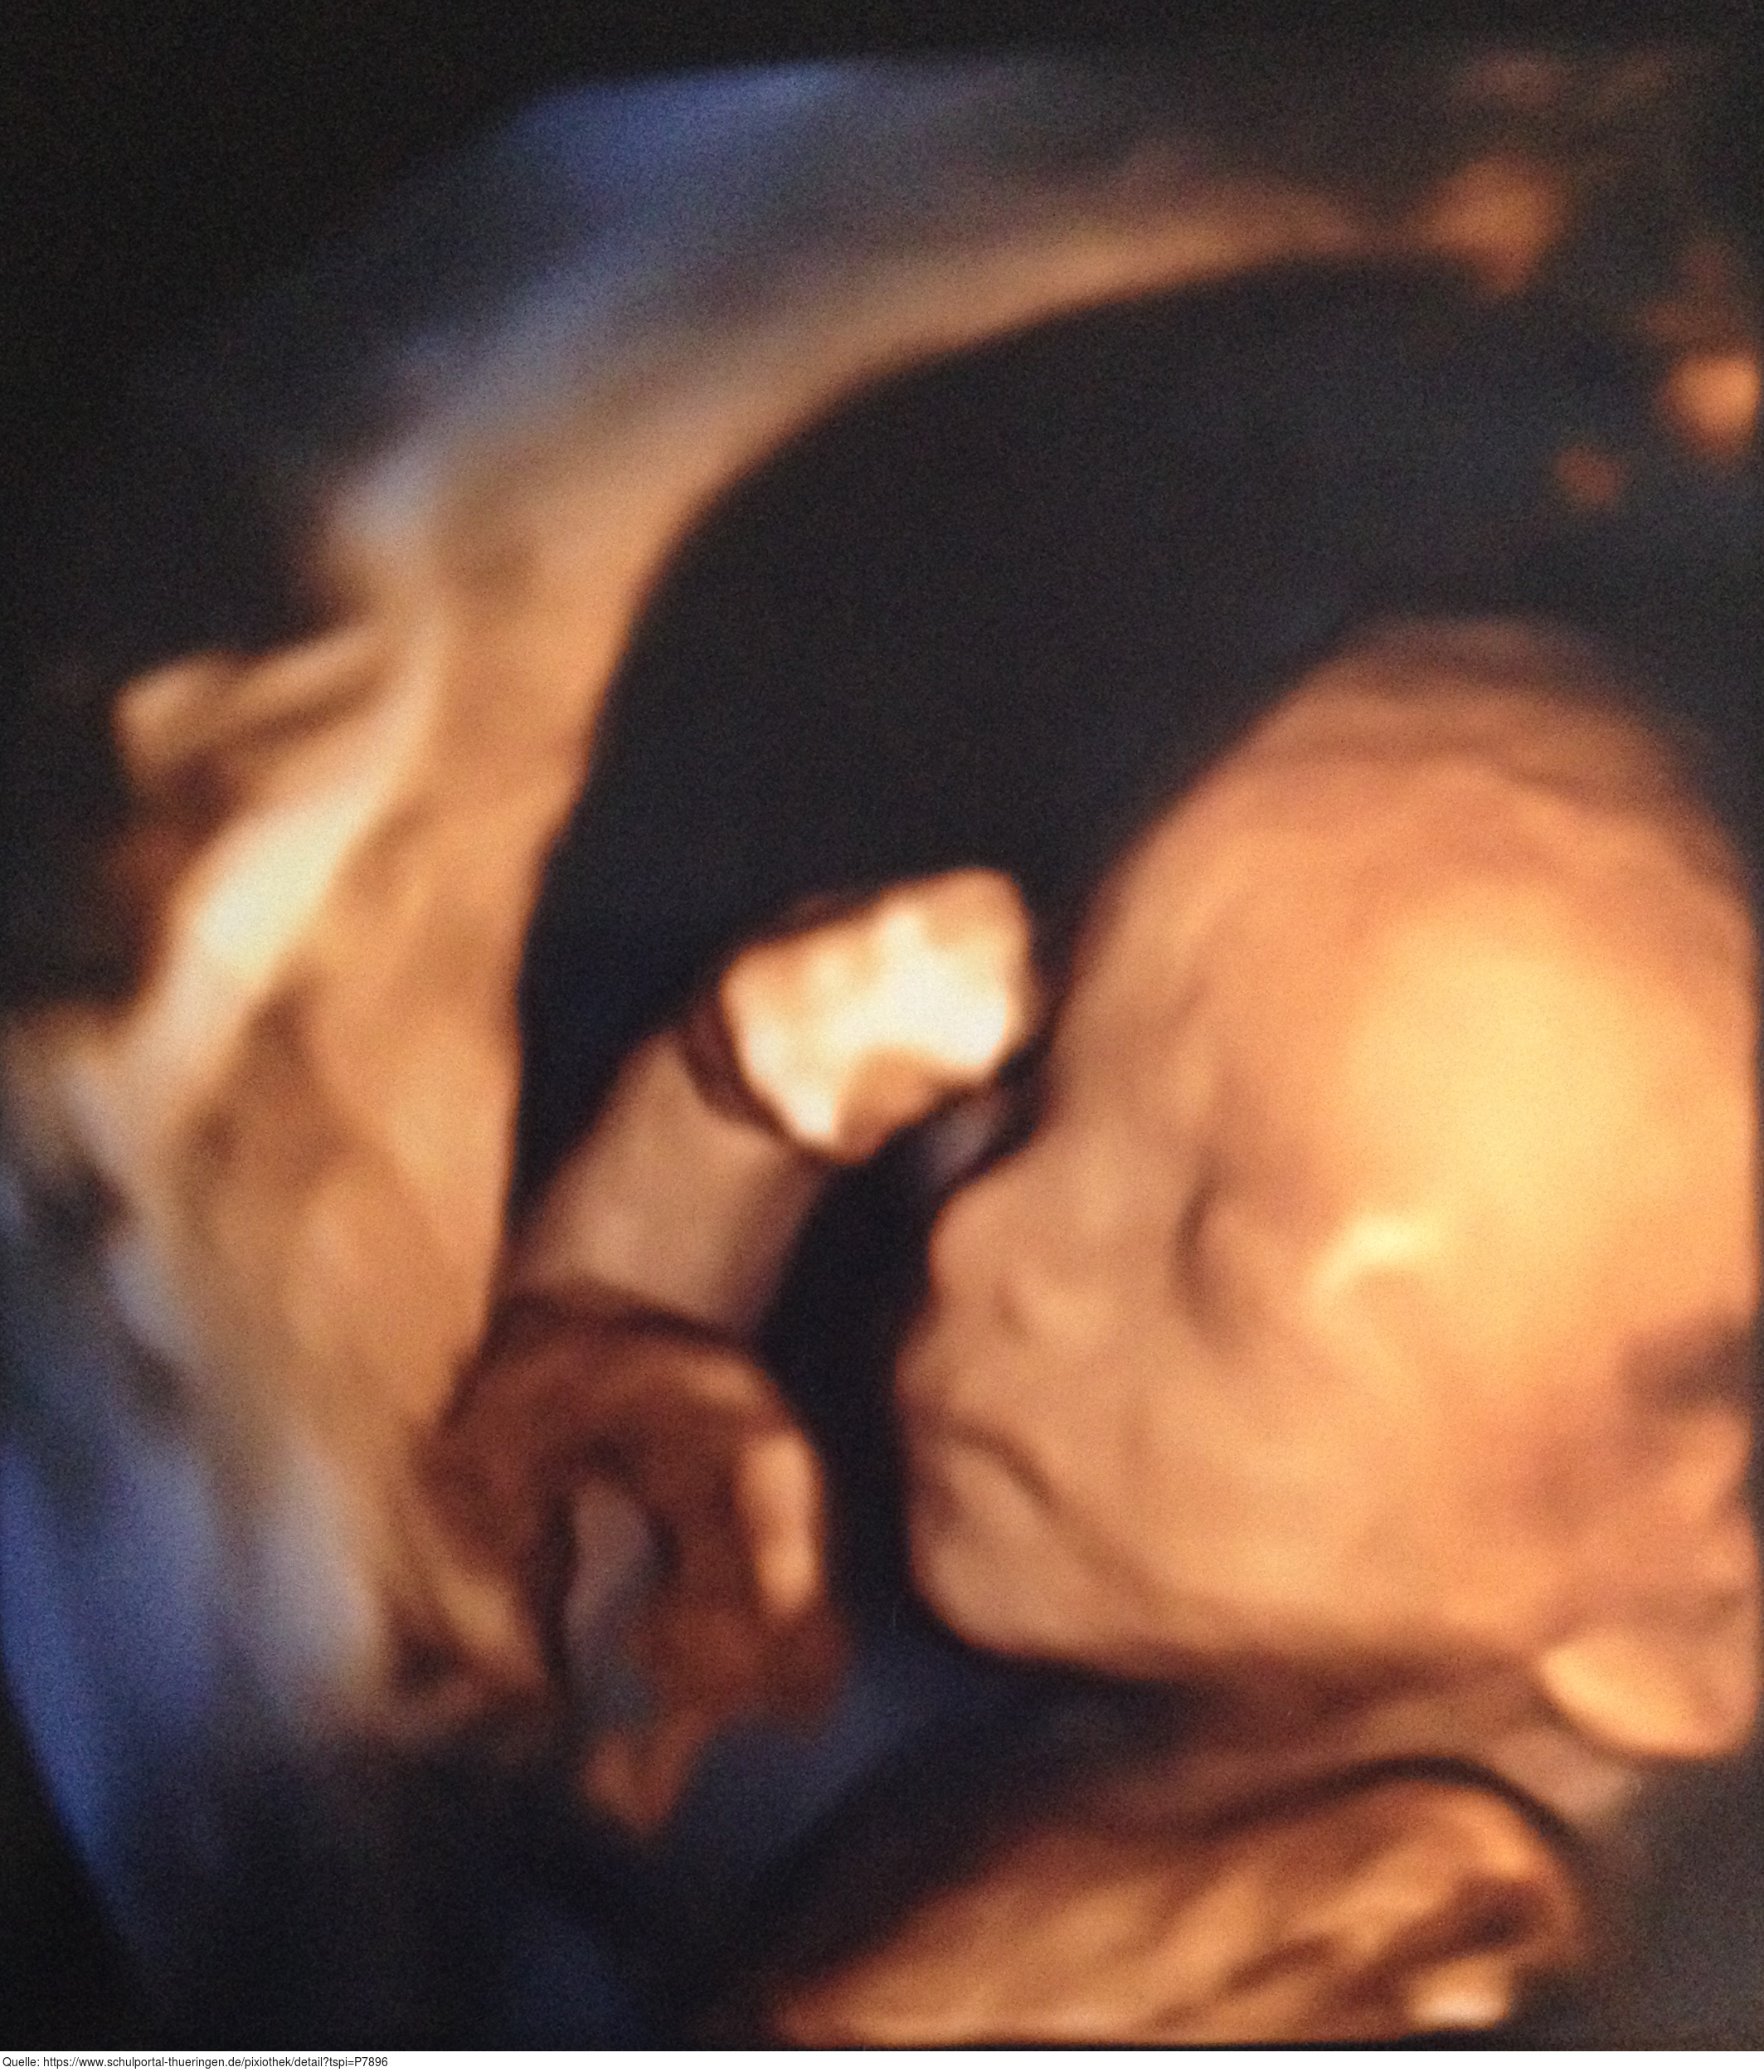

Das Bild zeigt ein Motiv aus dem Park an der Ilm in Weimar vom April 2020 in der Zeit des Lockdowns. Es gelten die Nutzungsbedingungen der Mediothek und Pixiothek.